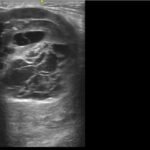

Patients commonly present to the Emergency Department for the evaluation of soft tissues masses of various etiology. Point-of-care ultrasound (POCUS) can aid in the initial evaluation of these masses to begin narrowing a given differential. Soft tissue sarcomas are a malignant neoplasm that frequently present in an extremity, and require close follow-up for the evaluation of metastasis and possible resection, among other treatment options. Being able to effectively differentiate between infectious, inflammatory, benign, or potentially malignant pathology for undifferentiated soft tissue masses is critical for Emergency Medicine clinicians to ensure patients receive appropriate treatment and referrals for definitive care.